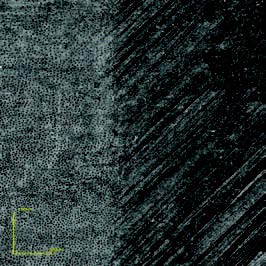

The OLS4000 allows the creation of high-resolution 3D images and requires no pretreatment or vacuum conditions of the sample. Thus, these images may be used for other analyses or even the continuation of an experiment. Captured images allow the observation of surface changes such as enamel prisms, dentin tubules, and eroded areas (Figure 2, 3, and 4, respectively).

Figures 3a and 3b: Dentin exposed to hydrochloric acid. 3a left side: Eroded dentin; 3a right side: Control area.

3b: Dentinal tubule exposition.